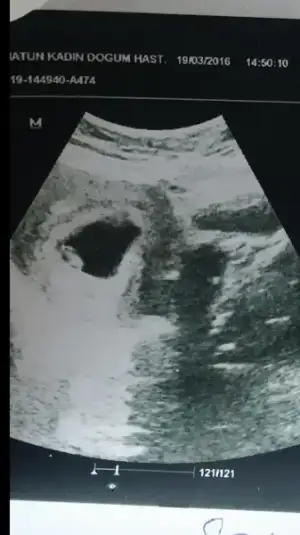

Arkadaslar bu resim 6+4 gunlukken. Daha oncekide ilk usg dede bu sekilde soldaydi sizce erkek mi kizmi:)) karindan yapildi bu arada ulturason:)